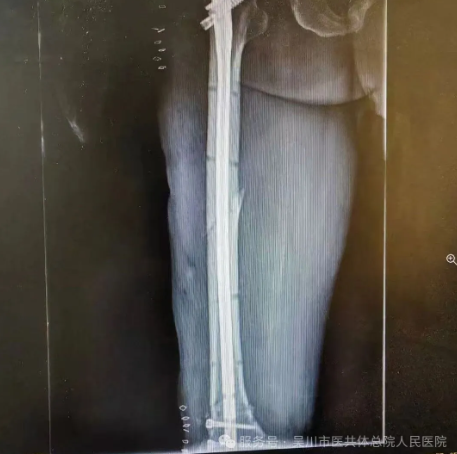

骨外科一区主任、主任医师李德强,立即带领专家团队对患者的各项身体指标、受伤情况等进行综合评估,缓解家属的焦虑情绪。最终决定为患者施行损伤控制手术,稳定患者的生命体征,待其血流动力学稳定后,再二期采用微创小切口的方式来修复骨盆以及股骨多段骨折。

这一技术是我院骨外科一区自主完成的创伤骨科中最高的四级手术之一,它的成功开展,意味着我院创伤骨科水平已达到三甲医院标准,彰显了我院在创伤救治领域深厚的专业底蕴和强劲的专业技术。